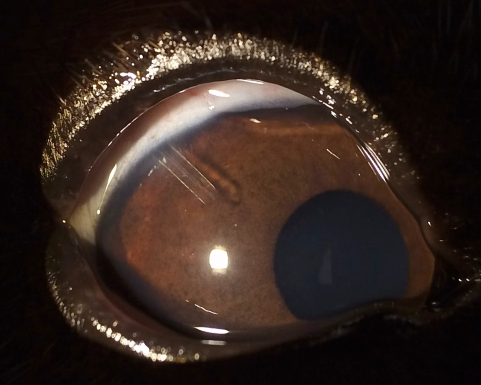

緑内障は眼の中の圧力(眼圧)が上昇し、視神経にダメージを与える病気で、短期間で視覚を失う可能性があります。

また、進行すると角膜が白く濁ったり、目が大きく見えるようになることもあります。